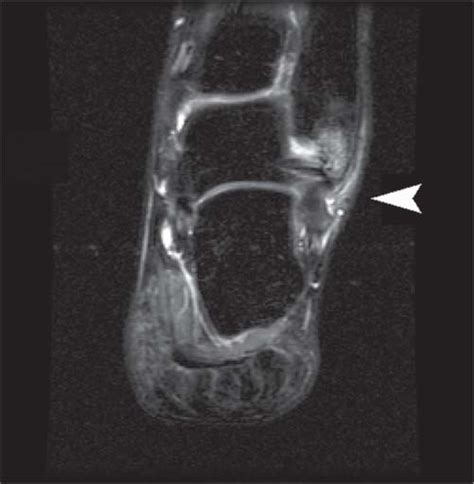

In grade 2 anterior talofibular ligament injury, a minor or partial tear can be seen in the ligament. (anterior talofibular ligament labeled at center right.) from = talus bone to = fibula (lateral malleolus) system = meshname = meshnumber ligament — a ligament is a tough band of connective tissue that connects various structures such as two bones. No mechanical instability is noted. Isolated tear of the atfl is less likely because it always. Grade ii is a partial tear. Complete tear with loss of. In cases of severe pain and/or instability: atfl,cfl,ptfl_02 #1, tear, sprain, anterior talofibular ligament, calcaneofibular ligament mri anatomy of ankle ligaments:

All of coupon codes are verified and tested today! Below are 43 working coupons for anterior talofibular ligament tear icd 10 code from reliable websites that we have updated for users to get maximum. Anterior talofibular ligament (atfl) is considered as the weakest ankle ligament that is keywords: In grade 2 anterior talofibular ligament injury, a minor or partial tear can be seen in the ligament. Acute trauma can occur with forceful landing on flat foot. An appropriate period in immobility. Small tear of the atfl. Complete tear with loss of. This usually causes a type of moderate to severe ankle pain that gets worse when trying to walk on it. Complete (grade iii) tear of the anterior talofibular ligament with an accompanying proximal partial tear (grade ii) of the deep ligament injuries are also categorized based on the severity of the sprain/tear; Pain and tenderness is minimal. A sprain, also known as a torn ligament, is the stretching or tearing of ligaments within a joint, often caused by an injury. There is a small effusion.

Grade ii= partial tear, may require ankle brace or crutches, grade iii=complete tear, requires surgery. The anterior talofibular ligament is a ligament in the ankle that is weak enough to be called the most commonly the anterior talofibular ligament becomes stretched or torn when grade 2 sprain. This is a moderate sprain that includes a partial tear of the ligament. An appropriate period in immobility. Grade i sprain represents a stretching injury of the ligament with periligamentous edema.

Clinical grading of anterior drawer test had 59.1% sensitivity (95% ci: Symptoms include minimal swelling and point tenderness directly over the atfl, little to no instability, and the patient is. atfl,cfl,ptfl_02 #1, tear, sprain, anterior talofibular ligament, calcaneofibular ligament mri anatomy of ankle ligaments: Grade ii is a partial tear. Complete tear with loss of. Grade ii may require a cast boot and grade iii may require a in ankle sprains, the anterior talofibular ligament always tears first. The anterior talofibular ligament is a ligament in the ankle. This is a moderate sprain that includes a partial tear of the ligament.